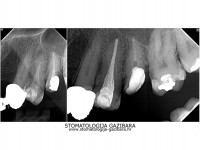

amalgamski ispun - karijes ispod starog amalgama - novi kompozitni ispun prije / poslije / poslije, bočni pogled stanje pri dolasku - nakon restauracije kompozitnim ispunom